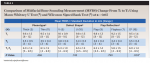

At T3, the mean radiographic marginal bone level (MBL) change of -0.3 ± 0.3 (-0.7 to 0) mm was noted on the mesial aspect of the implant, while -0.5 ± 0.5 (-2.0 to 0) mm was noted on the distal aspect of the implant, yielding an overall average MBL change of -0.4 ± 0.3 (-1.0 to 0) mm. There was no statistically significant difference in the mean MBL between the U-shaped (-0.6 mm) and V-shaped (-0.4) groups (P = .79). At T3, CBCT evaluation showed a mean facial marginal bone level (FMBL) of -0.6 ± 0.8 (-2.1 to 0.5) mm in relation to the implant platform. Except for a single site at the 2 mm level, facial horizontal bone thickness (CBCT-FHBT) at all sites in all levels was ≥1.5 mm (Table 1).

The mean overall changes of facial implant mucosal thickness (FIMT) from T1 to T2, facial implant mucosal level (FIML) from T0 to T3, and midfacial bone sounding (MFBS) from T1 to T3 were 1.2 ± 0.5 (1.6 to 2.9) mm, -0.4 ± 0.4 (-1.6 to 1.0) mm, and 6.0 ± 1.4 (4.0 to 8.5) mm, respectively (Table 2 through Table 4). Comparisons of tissue changes between different parameters (thick vs thin phenotype, V- vs U-shaped facial bone wall defect, and surgery with vs without full-thickness flap reflection) also are presented in Table 2 and Table 3. Regardless of phenotype, defect shape, or surgical technique, the mean FIMT values at T2 were comparable (2.3 mm to 2.4 mm), and all MFBS measurements at T3 were between 3 mm and 4 mm (Table 2 and Table 4). The mean FIML change of -0.4 mm and MFBS change of 6.0 mm translates to a mean vertical facial hard tissue gain of 5.6 mm.

The significance of a C-BG at the time of IIPP in maintaining facial mucosal level in the presence of a facial bone wall defect is also a point of discussion. Typically, it takes months for bone cells to migrate from the surrounding socket walls to encase or replace the grafted bone material within the extraction socket.23 Therefore, the initially grafted bone only serves as a matrix to support the soft tissue until vital bone formation occurs. During the early healing time, the most coronal portion of the bone at the facial entrance of the extraction socket will serve to maintain the FIML until grafted bone matures. In this study, facial contour bone grafting over the implant and facial bone wall defect (T1) resulted in a mean MFBS change of 3.5 mm ± 0.4 mm (T3), suggesting that the particulate bone graft material turned into solid, stable bone over time. It is interesting to note that regardless of tissue phenotype, defect shape, or whether the surgical procedure was done with or without flap reflection, all of the MFBS measurements at T3in all sites were between 3 mm and 4 mm (Table 3), indicating that the technique performed in this study could yield a predictable result. Moreover, because the platforms of the implants in this study were placed about 3 mm apical from the facial mucosal margin, the radiographic bone measurement from the implant platform (mean CBCT-FMBL [-0.7 mm]) and the bone sounding measurement (mean MFBS [3.5 mm]) confirmed that the facial bone was regenerated almost to the level of the implant platform. At T3, the mean FIML change of -0.4 mm and mean MFBS change of 6.0 mm also translate to the mean vertical facial hard tissue gain of 5.6 mm.

The importance of the facial-palatal implant position on the FIML cannot be overstated. A facially positioned implant can exhibit gingival recession three times greater than that of a palatally positioned implant.24 In general, from an incisal view, the implant should be placed palatally (engaging palatal bone) and within the confines of the extraction socket aligned with the arch form. Especially in situations where a facial bone wall defect is present, a palatally positioned implant allows for facial bone grafting to achieve appropriate vertical and horizontal underlying bone support for optimal peri-implant soft-tissue architecture. In the present study, CBCT assessment showed a mean FHBT of 0.6 mm, 1.5 mm, 1.9 mm, 2.5 mm, 2.7 mm, and 2.9 mm at 0 mm, 1 mm, 2 mm, 3 mm, 5 mm, and 7 mm apical to the implant platform, respectively. Creating an adequate bone thickness with a contour bone graft over the facial aspect of the implant is significant, as Monje et al reported that the chances of implant marginal bone loss were significantly reduced with a minimal facial bone thickness of 1.5 mm,25 thereby lessening the risk of surface contamination and peri-implantitis.26,27

A thin soft-tissue phenotype has been associated with an increased risk of facial implant mucosal dehiscence (ie, recession).19,24,28 Numerous studies have shown the benefits of C-CTG simultaneous with IIPP.17,21,23,29,30 Thickening the FIMT not only can minimize facial mucosal recession, but it may also conceal the underlying implant and/or implant restorative materials. Moreover, thickening the facial mucosa may override the need for underlying facial bone support. A 1-year follow-up study on IIPP and C-CTG on maxillary anterior implants showed an average increase in FIMT of 1.4 mm (0.4 mm to 2.7 mm).29 In the present study, a comparable mean FIMT gain of 1.2 ± 0.5 (0.3 to 2.0) mm with C-CTG grafting was noted after a mean follow-up time of 8.9 (6 to 15) months. Irrespective of initial (T1) soft-tissue phenotype, the average resulting (T2) FIMT of both thick-tissue and thin-tissue phenotype groups was similar (2.3 ± 0.4 mm; Table 2), indicating that thin soft-tissue phenotype is likely to benefit more from this phenotype modification procedure. The changes in FIML and MFBS were comparable between thick and thin phenotype groups (Table 3 and Table 4).